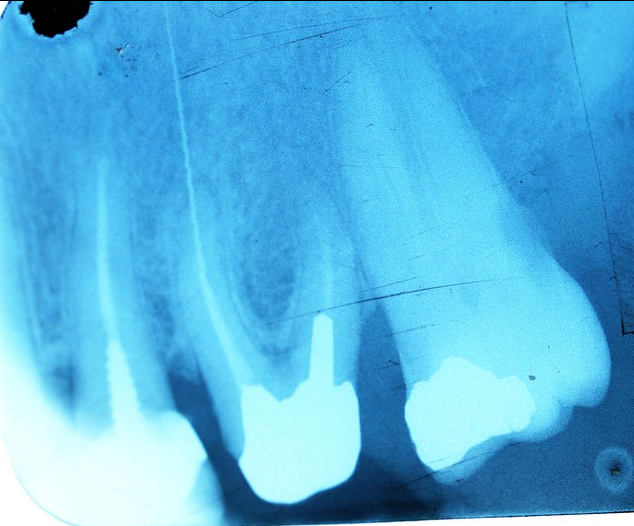

J'ai bloqué un openeur dans un canal ... du coup, j'ai inversé le sens de rotation de mon contre angle pour le débloquer. Et j'ai oublié de le mettre dans le bon sens au moment de thermo compacter.

Le cas était amusant, le confrère qui avait obturé n'avait pas trouvé le canal lingual.

Ça pue quand même un peu ton truc là… ton instrument traverse du tissus infectieux, le cône d’à côté dépasse lui aussi… et pour couronner le tout, la résection a cet endroit si ça foire c’est pas jojo. Ça sent le titane…

Sinon pour le compacteur pété, comme on dit, shit happens mais effectivement vu qu'il est sorti de la racine et qu'il baigne dans la LIPOE, m'est avis que c'est kaput.